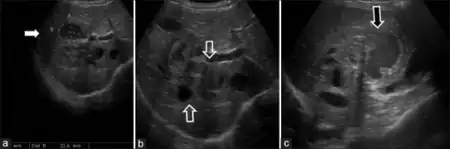

| a-c)Sonography images of male child diagnosed with hepatic visceral larva migrans | |